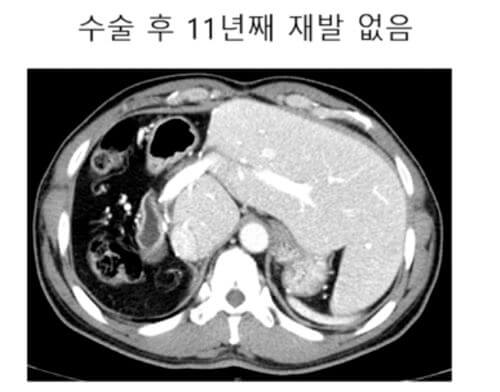

사진에서 화면에 보시는 것처럼, 이분이 거의 그 10년 전에 오신 분인데, 오른쪽 간에 10cm 넘는 큰 간암이 있고 주변에도 위성 결절이라고, 그래서 조그만 간암이 막 오른쪽 간에 많이 퍼져 있는 그런 분이었습니다.

이분은 방사선 색전술이라고 하는 색전술의 하나의 방법 시술로 해서 종양이 매우 많이 줄어들고 괴사가 되고 해서 결국은 오른쪽 간을 절제하는 수술하고, 지금 7년 8년 이상 재발 없이 생존하는 분들도 있다.

이런 환자들을 볼 때마다, 이렇게 좋은 치료 경험을 갖게 되는 환자분들이 많으면 참 좋겠다는 생각을 하게 됩니다.